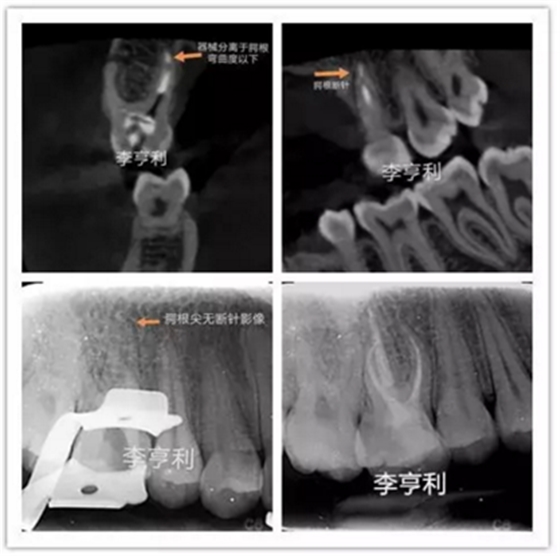

李亨利取出腭尖斷針的病例

在根管治療前,一定要充足地預(yù)估難度,謹(jǐn)記根管解剖,并且要熟悉自己臨床使用器械的設(shè)計(jì)、尺寸和參數(shù)。雖然說斷針本身并不影響治療效果,但往往都是因?yàn)榛颊叩膫€(gè)人意愿,最后選擇取出斷針。如果難度超過術(shù)者自身的能力,就一定要轉(zhuǎn)診至??频难荔w牙髓醫(yī)生進(jìn)行處理。